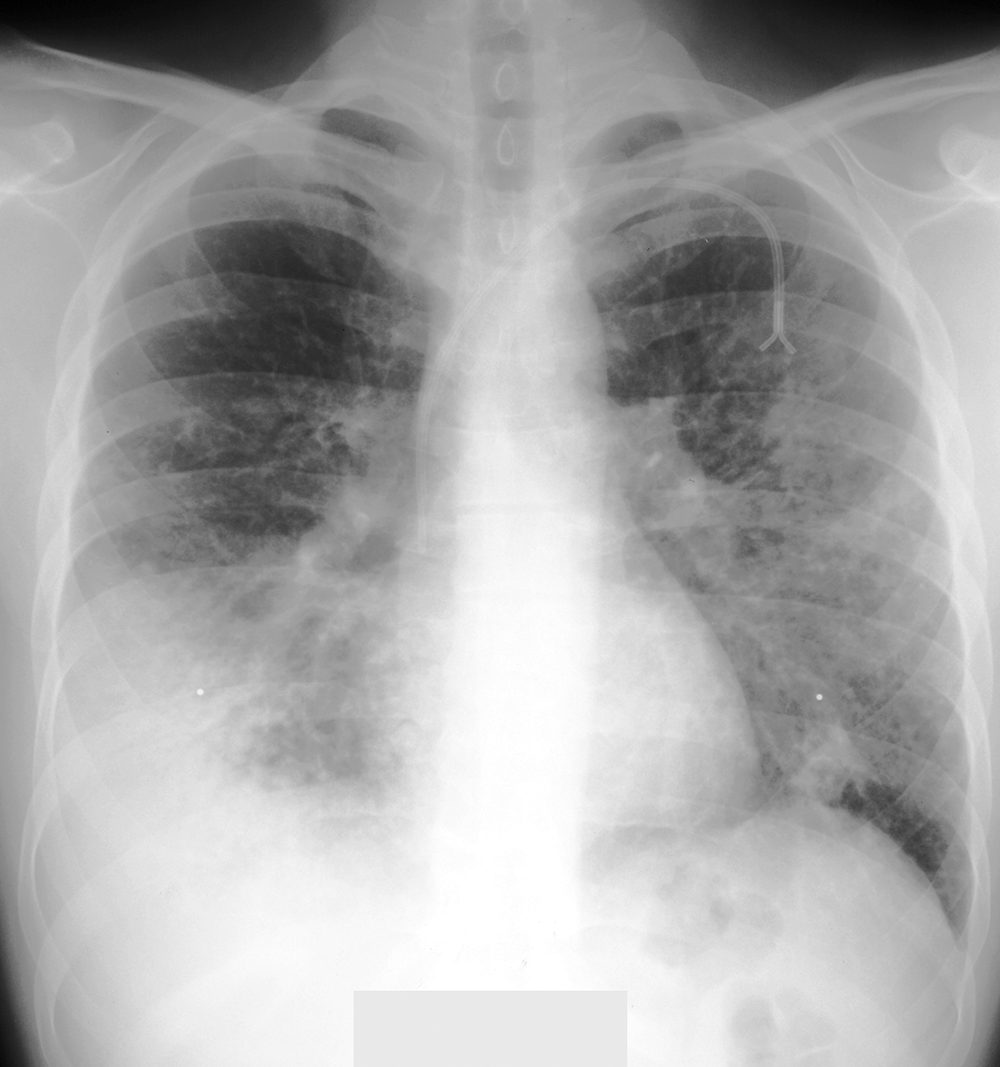

Topic 1

alternate diagnosis to consider for PNA

Further Explanation: